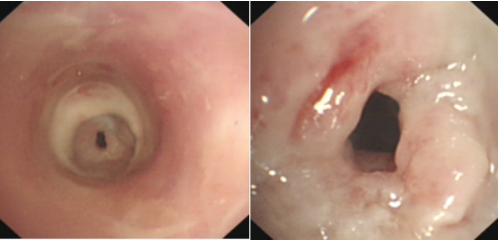

查体:胸闷气短,端坐呼吸,指脉氧下降,三凹征明显,气管听诊区可闻及双相哮鸣音,PaO2 50 mmHg。镜下可见气管内新生物堵塞气道(图11)

图片

图11  气管镜下所见

MDT意见:①无法外科手术;②端坐呼吸、气短明显,全麻风险极高;③肿块组织大,硬镜旋切出血及管腔阻塞的风险极大。在此情况下,治疗团队选择了一种既能降低手术风险,又可以处理大气道阻塞的方法——清醒VV-ECMO+硬镜旋切。切除的肿瘤组织较多且大,呈黏液样表现(图12)。手术前后对比发现,患者气道狭窄明显改善(图13)

图12  切除的肿瘤组织

图13  患者手术前后比较